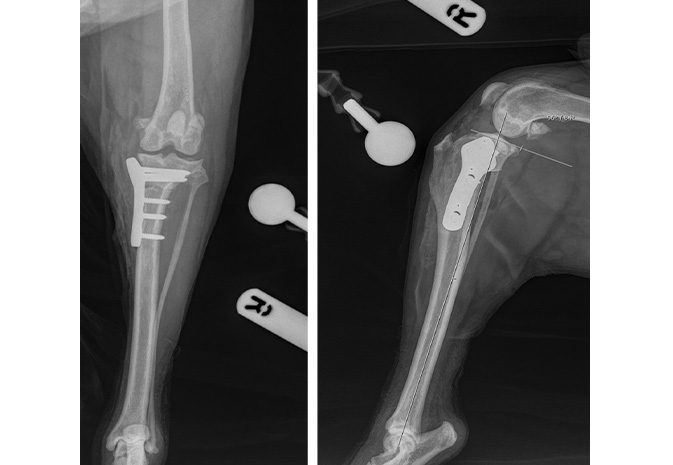

After surgery, plate and screw placement is checked and new angles are measured

Colin was taken to surgery on the same day and a medial parapatellar approach was made to the right stifle joint. Arthrotomy confirmed complete rupture of the cranial cruciate ligament with meniscal damage that was removed at this time. A right TPLO was performed. The bone was fixedusing a 3.5mm locking TPLO plate.

Post-operative radiographs showed good reduction of the osteotomy and implant positioning. 6 weeks post-operatively, repeat radiographs were taken to ensure healing and proper positioning. Colin received the all-clear and is now doing very well.